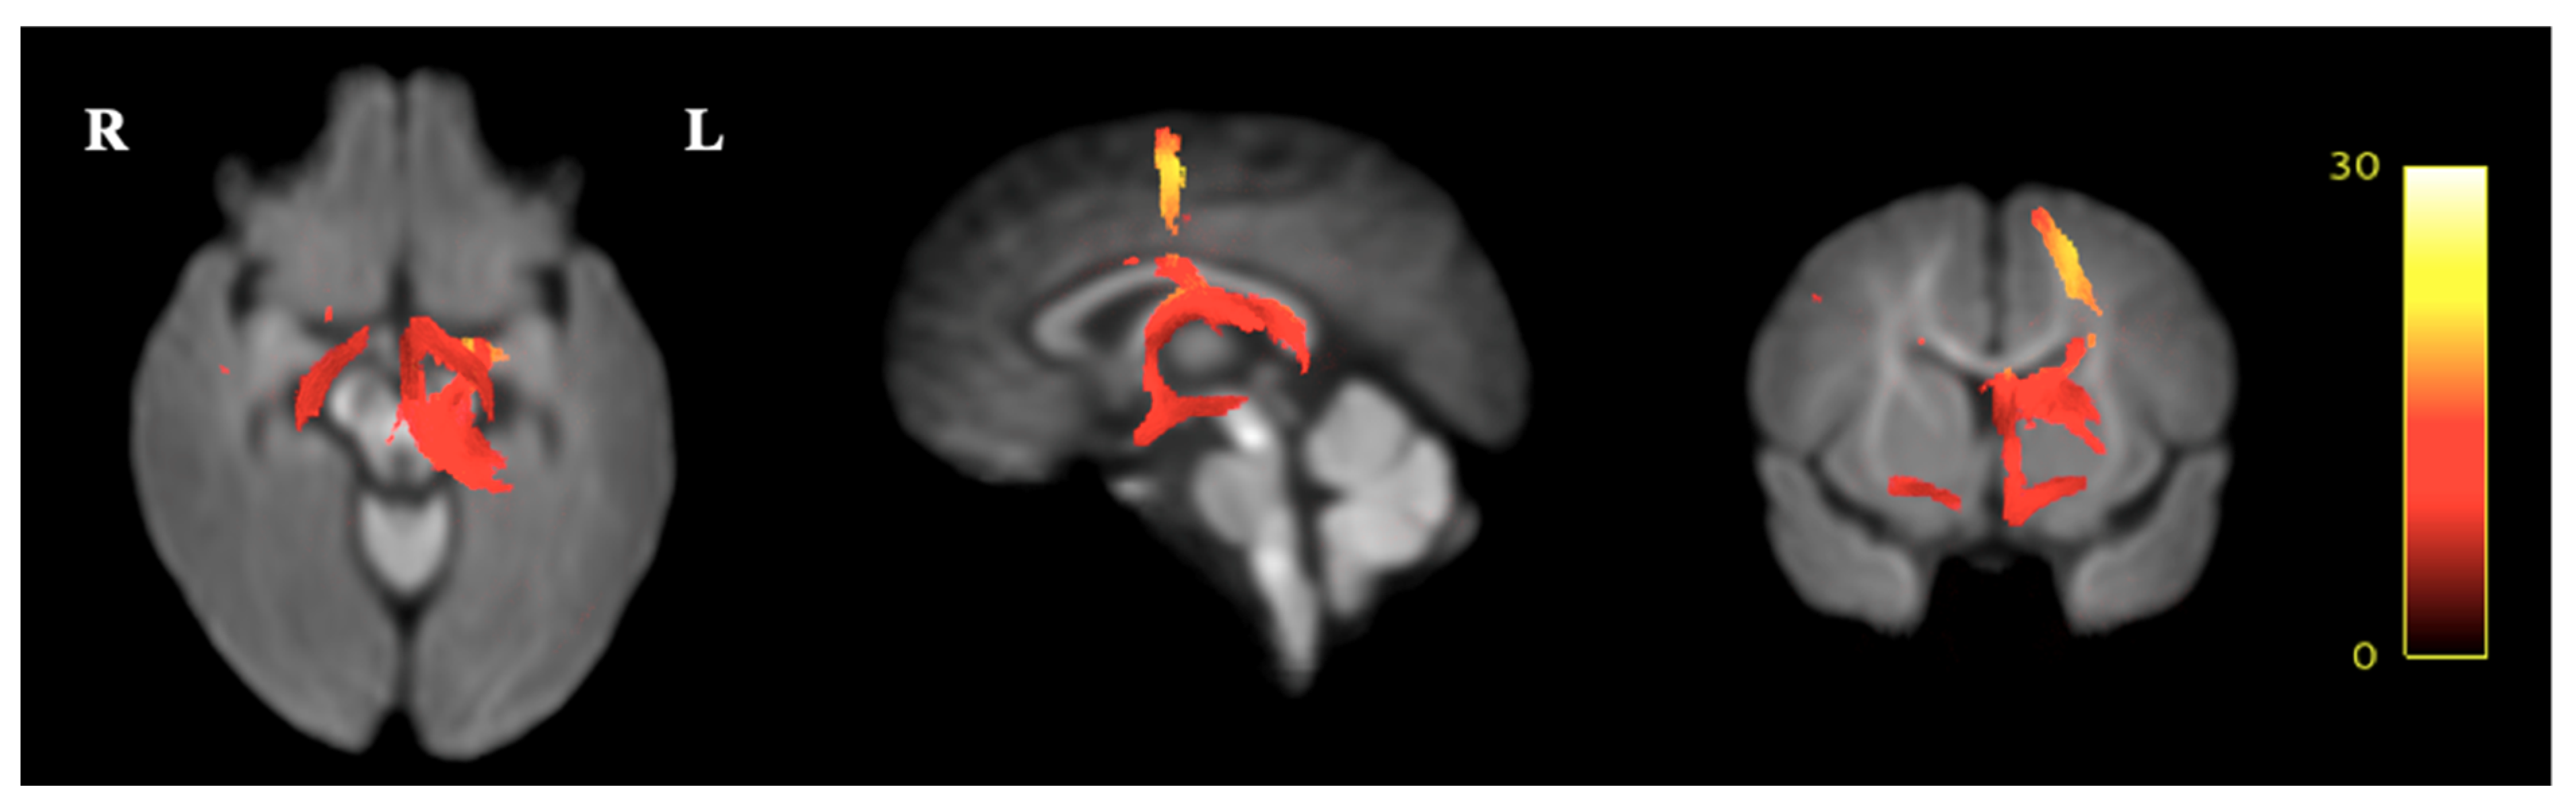

2.5.3. Fixel-Based Analysis

3.4. Fixel-Based Diffusion